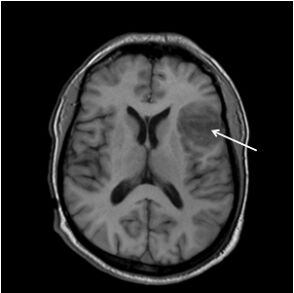

11.吳先生因車禍造成腦創傷並且昏迷,其兩側肢體出現僵直的姿勢(rigidity posture)反應,送醫經影像檢查發現其腦部有出血現象,受損位置如圖所圈示。下列何者為吳先生會出現的肌張力反應? (A)後弓反張:頸部及軀幹有過強的伸直張力 (B)去皮質僵直:上肢屈曲及下肢伸直反應 (C)去大腦僵直:四肢呈現伸直反應 (D)去大腦僵直:上肢伸直及下肢屈曲反應

33.中風男性的核磁共振影像如下圖所示,最有可能的診斷為何? (A)小洞梗塞型中風(lacunar stroke)(B)前大腦動脈梗塞型中風(C)中大腦動脈梗塞型中風(D)蜘蛛膜下腔出血

34.承上題,以下有關此病患症狀之描述,何者最為正確? (A)肢體偏癱並有感覺障礙,上肢比下肢嚴重,合併有失語症(B)肢體偏癱並有感覺障礙,下肢比上肢嚴重,合併有尿失禁(C)肢體偏癱並有感覺障礙,僅有上肢受影響,合併有失用症(D)肢體偏癱無感覺障礙,僅有下肢動作受影響